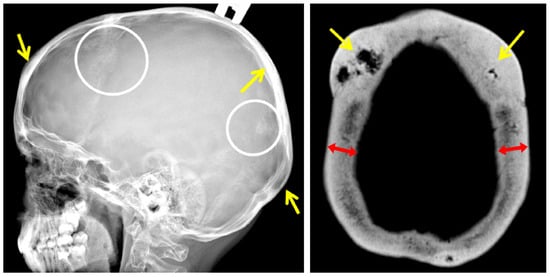

An X-ray examination of the wrist bones, performed due to short stature (−1.9 standard deviations) in the cousin of the F1 III-1 proband, revealed relative shortening of the fourth and fifth metacarpals (Figure 3).

The analysis of phenotypic manifestations in the patients observed in this study and presented in the literature indicates polymorphism of the clinical manifestations of the CDL in patients with the recurrent variant in the SGMS2 gene. The presence of significant clinical polymorphism (including intrafamilial) in all of these cases allows us to conclude the possible effect of the genetic background and epigenetic modifiers on the formation of the disease phenotype. In most patients, the first fractures occur in childhood; however, the age of clinical manifestation widely varies. Differences in the height indicators of patients with the presence of multiple fractures were noted. In some patients, height was within the normal range, while in others, the growth was reduced by more than 2 SD. Along with skeleton involvement, some patients have symptoms of damage to the nervous system in the form of migraine, cephalgia, recurring paralysis of the facial, trigeminal, and oculomotor nerves, carpal tunnel syndrome, dystonia, and tremor. However, the severity of skeleton and nervous system involvement in patients with nonsense and two missense variants differed significantly. In two patients with p.Ile62Ser or Met64Arg variants reported in the literature, spontaneous fractures occurred in the neonatal period and led to decreased height as a result of deformations of the spine and limbs. The radiological examination revealed signs of spondylometaphyseal dysplasia. The more pronounced symptoms of nervous system damage were also noted. In addition to transient cranial nerves paralysis, patients were diagnosed with sensory neuropathy, hearing loss, and tendon hyporeflexia. The pathogenesis of CDL has not been fully understood yet, but it is assumed that neurological symptoms are associated with a dysfunction of the gene product, the enzyme sphingomyelin synthase, which is involved in the synthesis of myelin in the structures of the nervous system. Some of the patients examined by us (4/11) had transient recurrent facial nerve paralysis in adulthood, affecting both the upper and lower parts of the face that resolved on their own within a month. Two patients from the second family suffered from headaches since childhood. In addition, the presence of congenital bilateral glaucoma in one of the examined patients was noted. Interestingly, congenital glaucoma was also reported in one patient with CDL in a study by Pekkin M. et al. in 2019 [4]. Undoubtedly, this observation requires further accumulation of clinical data in patients with CDL. It should be noted that in the spectrum of phenotypic manifestations, serious damage to the teeth was found in some of the patients with a severe course of the disease, which led to their early destruction, wearing out of the incisal edges, and yellowing of the enamel, although other patients did not have the signs of teeth involvement. Another additional finding in CDL was a shortening of the fourth–fifth metacarpals previously reported by Jaakkola E. et al. [15]. We were able to detect similar features in the cousin of the proband in the first family. As the disease is quite rare, it is necessary to describe in detail all the phenotypic characteristics of patients with various types of variants in the SGMS2 gene, which will help to optimize its diagnosis.

Figure 3. Radiograph and appearance of the hand of the 7 y.o. patient (F1 III-1) with brachymetacarpia of the fourth and fifth digits: relative shortening (white arrows) of the fourth and fifth metacarpals to compare with the metacarpal heads line (blue line).